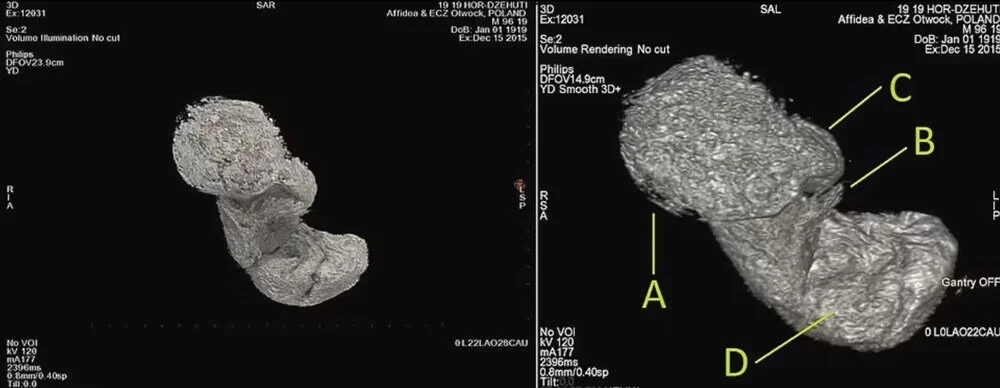

Polonya'daki Varşova Üniversitesi'nden araştırmacılar, geçen yılın Nisan ayında CT ve X-ray taramaları kullanarak doğmamış çocuğun kalıntılarının varlığını ortaya çıkardı.

Journal of Archaeological Science adlı bilimsel dergide yakın zamanda yayımlanan çalışmada mumya ile ilgili araştırmanın yeni bulguları paylaşıldı.

Bilim insanları, söz konusu kadın mumyasının içerisinde bir fetüs içeren ilk örnek olduğunu söyledi. Ayrıca mumyanın, Aralık 1826'da Varşova Üniversitesi'ne bağışlayan Jan Wężyk–Rudzki tarafından Mısır'dan satın alındığı aktarıldı.

Kadın mumyası ve doğmamış çocuğu hakkındaki çalışma, Polonya'nın Varşova Üniversitesi'nden arkeolog ve paleopatolog Marzena Ożarek-Szilke ve meslektaşları tarafından üstlenildi.